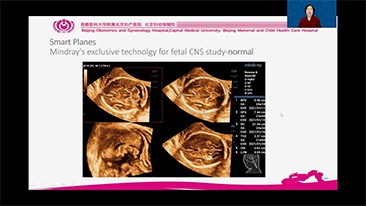

Geoptimaliseerde workflows in gynaecologie en verloskunde zijn noodzakelijk ter ondersteuning van grote pati?ntenvolumes aan screeningbezoeken voor vrouwen. Misvormingen van het centrale zenuwstelsel (CZS) zijn bijvoorbeeld een van de meest voorkomende aangeboren afwijkingen. Als gevolg van verschillende beeldvormingscondities, zoals een slechte foetale positie, is de MSP zeer moeilijk te vinden in een 2D-echografie. Daarom kunnen geautomatiseerde detectie en metingen de scaneffici?ntie sterk verbeteren.